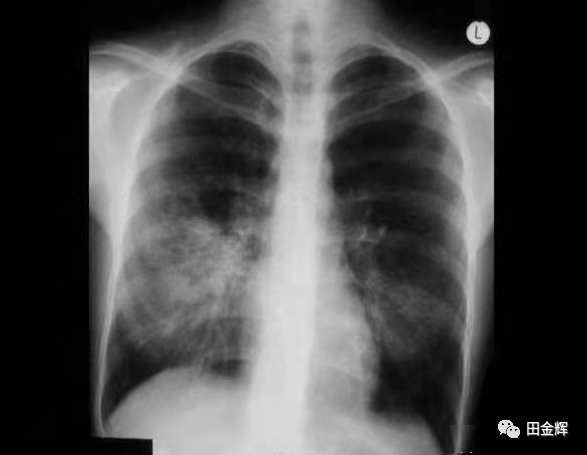

◆ 肺部体征与影像学改变不一致:

肺部听不到啰音

所谓肺部体征是指咳嗽非常明显及严重,由于支原体感染往往侵犯的是肺间质,炎症渗出并不在气管、支气管及肺泡内,因此,用听诊器往往听不清有明显的啰音。

通过拍胸片显示:大部分肺下叶的大叶性肺炎及肺间质炎的表现,即呈现不规整的大片状、絮状浸润性阴影,且肺门阴影增大增重,系淋巴结肿大表现。这是诊断支原体肺炎的重要依据之一。也就是说听诊与胸片的表现似乎是矛盾的。

小儿支原体肺炎胸片改变

医生当然不会拿这种非特异性检查作为诊断依据的,

一般是通过询问病史、了解临床特征来初步判断,比如咳嗽持续2~3周、且进行性加重;

一般抗生素治疗均无效,临床咳嗽剧烈而肺部往往听不到啰音。然而,要诊断支原体肺炎就要依据胸片+病原学检测。

4、最重要的:X线胸片肺纹理正常或稍许增多,肺门正常。